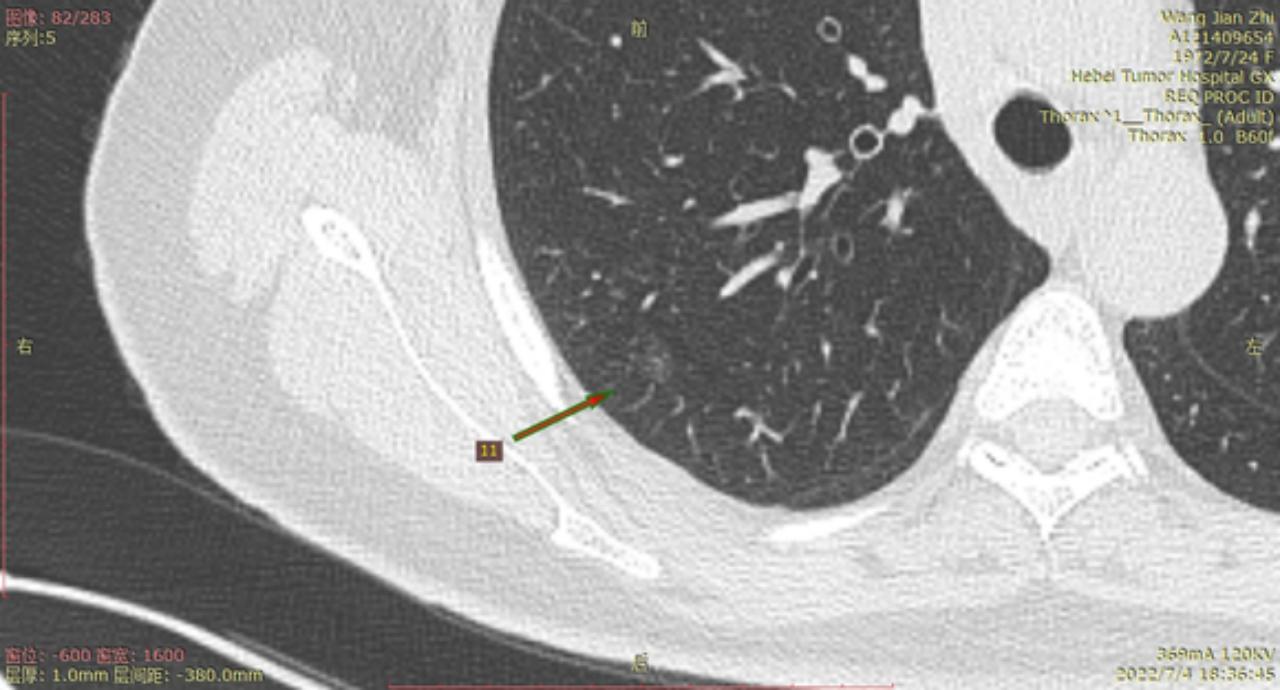

今年6月22号河北省人民医院进行CT检查后,报告双肺多发磨玻璃结节及微小结节以右肺为多,建议六个月后复诊。我于7月3号在河北省四院胸外科就诊,大夫建议复查薄层CT,7月4日CT结果报告示两肺多发结节,部分为磨玻璃密度,建议三个月复查,省四院的主任看了CT后有的建议立即住院手术,有的建议三个月复查,专家意见不一致,后来我看了主任的贴吧,首次发现肺结节先口服莫西沙星,三个月后再复查的贴吧,就没有立刻手术,从7月4日开始口服莫西沙星,现已完成15天疗程。等待复查的这一段时间里,总是担心大的结节已有浸润,请主任给予帮助,看看我的CT,给出我治疗建议,麻烦主任了!

结4-5

结8-11